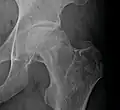

Radiografía de una osteonecrosis de la cabeza femoral izquierda. Hombre de 45 años de edad con SIDA. -